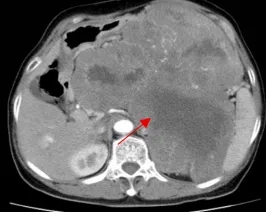

70岁、76岁、82岁,河北医大二院成功实施三例高难度腹膜后巨大肿瘤切除术

箭头示为患者一的腹膜后肿瘤